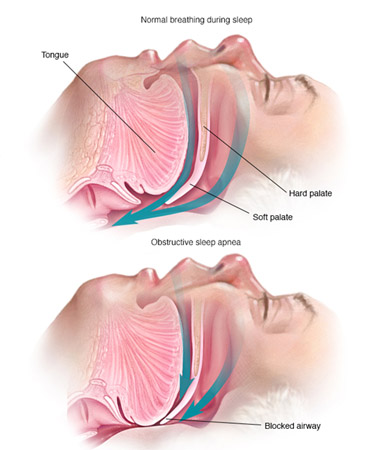

Sleep apnea is a sleep disorder characterized by pauses in breathing or periods of shallow breathing during sleep. Each pause can last for a few seconds to a few minutes and they happen many times a night. In the most common form, this follows loud snoring.

Loud and chronic snoring almost every night.

Loud and chronic snoring almost every night. Choking or gasping for breath during sleep.

Choking or gasping for breath during sleep. Pause breathing

Pause breathing Waking up at night feeling short of breath

The purpose of a dental appliance to treat sleep apnea is to maintain an open airway while sleeping.

A sleep apnea oral appliance keeps the airway open by preventing the jaw and tongue from falling back during sleep. By reducing the air obstruction, a dental appliance can correct sleep apnea and snoring.